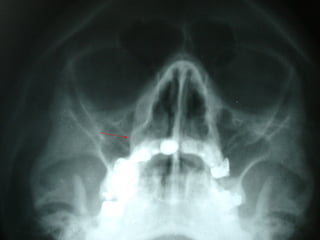

En el estudio radiográfico determinamos que el factor causal fué un foco séptico

dentario a nivel de segundo molar inferior izquierdo.